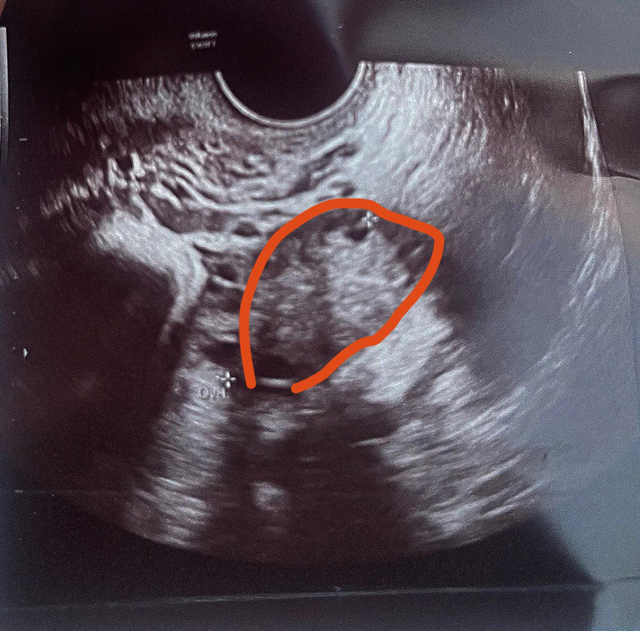

PCOS ovaries ultrasound

What the thing circled in red could be ?

Like why is there many bubbles ?